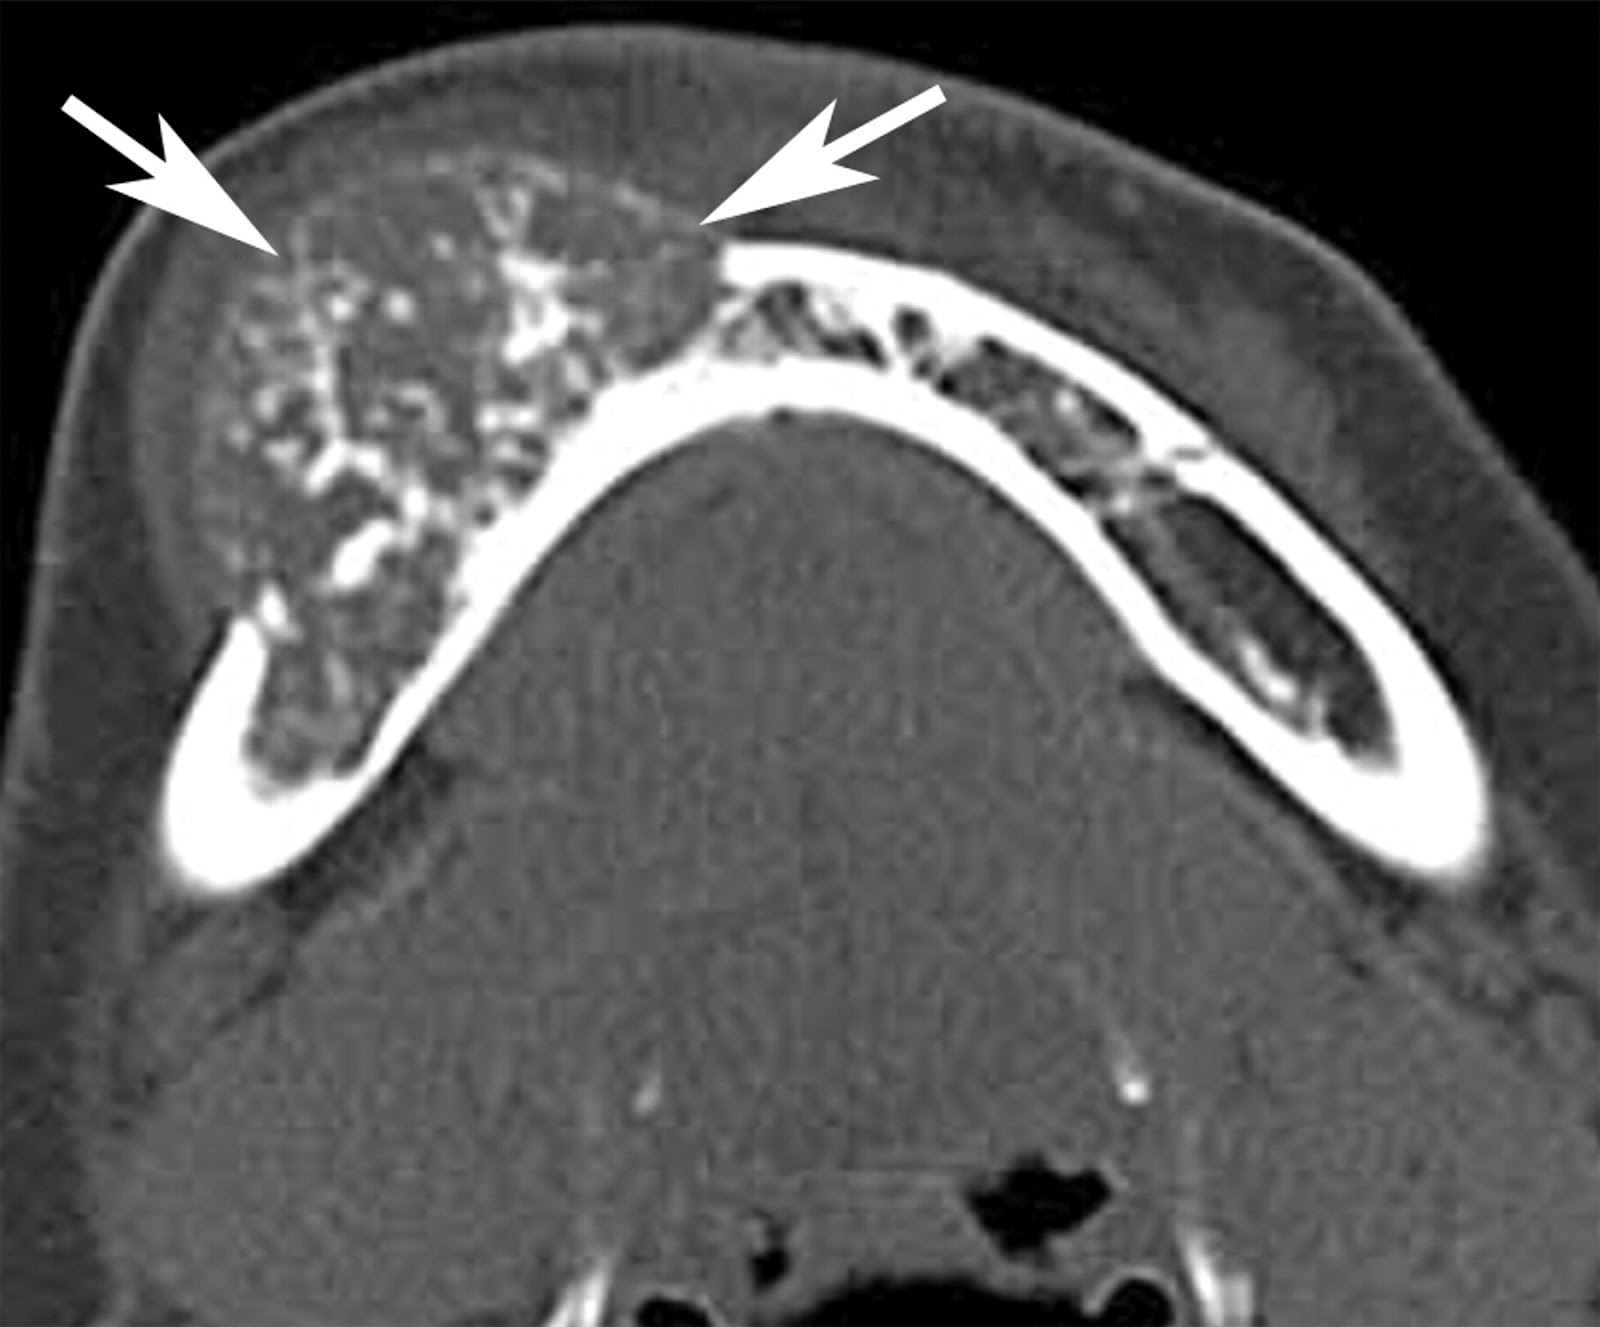

the sinus. Computed tomography scan demonstrating a mixed

radiolucent –radiopaque lesion (C). Cut surface of the gross